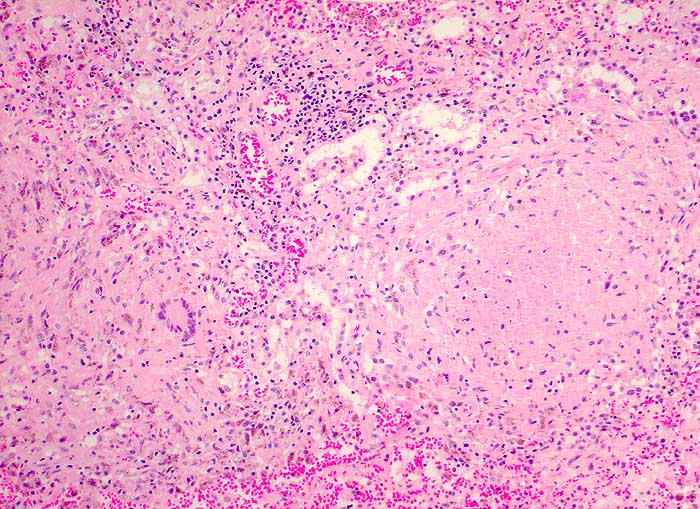

PathoPic – image database / PathoPic ID 5515 - Tuberkulose

Tuberkulose

Verkäsende Granulome mit Langhansriesenzellen.

Autopsiebefunde: Miliare Streuherde in Lunge, Milz (Dm bis 4mm), Nieren, Nebennieren, Ileum terminale und Zoekum (Tuberkulosepsis) mit Nachweis säurefester Stäbchen. Lymphknotentuberkulose zervikal beidseits (Dm bis 2x1cm), peribronchial beidseits, paraaortal abdominal (vor allem peripankreatisch), mesenterial und ileozökal (Dm bis 2x2cm). Nachweis von Mycobacterium tuberculosis in Abstrich von Milz und Lunge sowie in der broncho-alveolären Lavage 2 Wochen vor dem Tod. Käsige Pneumonie beider Lungen. Fibrinöse Pleuritis beidseits.

Generalisierte Lymphadenopathie, Stomatitis, HIV positiv.

Während bei immunkompetenten Patienten der Halslymphknotenbefall meist auf einen Primärinfekt im Bereich der Mundhöhle (Typ Bovinus) hindeutet, sind bei HIV Patienten die Lymphknoten wahrscheinlich im Rahmen einer generalisierten hämatogenen und lymphogenen Tuberkulose befallen (Miliartuberkulose).